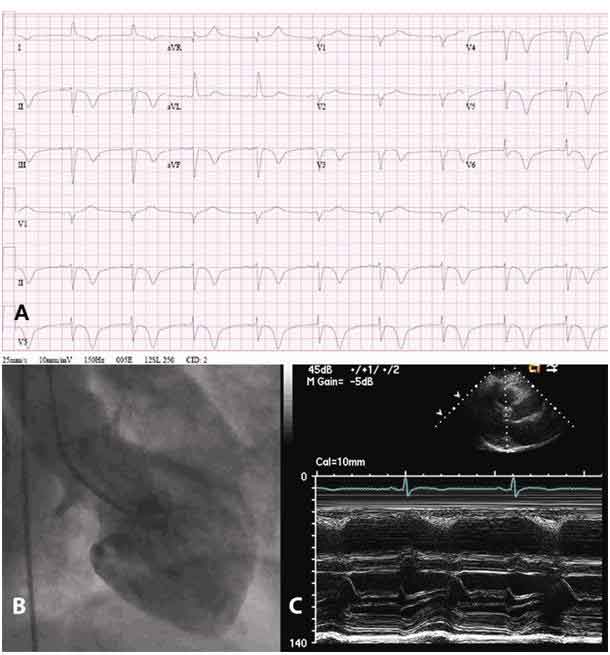

E’ per questo motivo che spesso viene assimilata al “crepacuore”. Un team di cardiologi, Leda Galiuto, Alberto Ranieri De Caterina, Angelo Porfidia, Lazzaro Paraggio, Sabrina Barchetta, Gabriella Locorotondo, Antonio G. Rebuzzi del dipartimento di Medicina cardiovascolare dell’Universita’ Cattolica-Policlinico Gemelli di Roma, guidato da Filippo Crea, hanno individuato il meccanismo che e’ alla base di questa curiosa patologia e hanno appena pubblicato un articolo sullo European Heart Journal, rivista della European Society of Cardiology. Un articolo che e’ gia’ fra i cinquanta piu’ letti nel settore. “Nell’80% dei pazienti i sintomi rientrano spontaneamente dopo un paio di settimane senza lasciare traccia – spiega Filippo Crea – mentre negli altri casi il danno persiste. Il punto e’ che il danno causato dalla sindrome e’ nel cuore, ma non nelle coronarie. Quello che noi abbiamo cercato di spiegare e’ il meccanismo che porta all’insorgenza di questi sintomi”. Per effettuare questo studio il gruppo guidato da Crea ha studiato quindici donne di eta’ media 68 anni per un mese. Grazie a questo studio, per la prima volta si e’ riusciti a individuare il meccanismo fisiopatologico della malattia. “Ci siamo concentrati sulla regione apicale del cuore – spiega la prima autrice Leda Galiuto, ricercatrice presso l’Istituto di Cardiologia della Cattolica – perche’ e’ li’ che e’ ubicata la disfunzione, tanto che il cuore assume la caratteristica forma a palloncino o, come hanno osservato i giapponesi, a forma di cesta per raccogliere i polipi, il Tako-Tsubo e’ appunto il nome di questa cesta in giapponese”. L’ipotesi dei ricercatori era che il meccanismo che condiziona la disfunzione risiede nello spasmo dei piccoli vasi coronarici, il cosiddetto microcircolo coronario. “Per dimostrare la veridicita’ della nostra ipotesi abbiamo utilizzato l’ecocontrastografia miocardica, una metodica di cui siamo pionieri e che consente di studiare in modo selettivo, sicuro, poco costoso e a letto del paziente proprio il microcircolo coronario”, spiega Galiuto. “Il microcircolo gioca un ruolo importante nelle malattie cardiache – aggiunge l’ordinario di Cardiologia della Cattolica Filippo Crea – e l’intensa vaso costrizione di questi piccoli vasi non si puo’ normalmente apprezzare in una coronarografia”. I ricercatori sono riusciti anche a dimostrare che questo spasmo microvascolare e’ reversibile e che una volta superata la fase acuta, si risolve anche la disfunzione microvascolare alla base dei sintomi osservati. “Nel paziente normalmente non rimangono danni perche’ la riduzione nell’apporto di sangue e’ si’ abbastanza grave da non fornire energia sufficiente al cuore per contrarsi, e di qui la forma ‘a palloncino’, ma non cosi’ grave da determinare la morte delle cellule cardiache come invece avviene in un infarto”, conclude Crea.